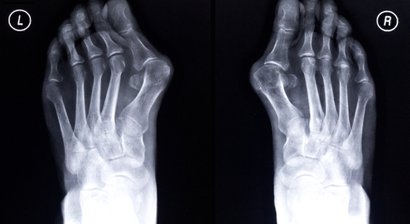

Hallux valgus

Bei einem Hallux valgus handelt es sich um eine Fehlstellung der Großzehe im Grundgelenk nach außen. In vielen Fällen geht die Fehlstellung der Großzehe mit einer Spreizung im Mittelfuß einher. Mit fortschreitendem Verlauf verliert die Großzehe immer mehr an ihrer...